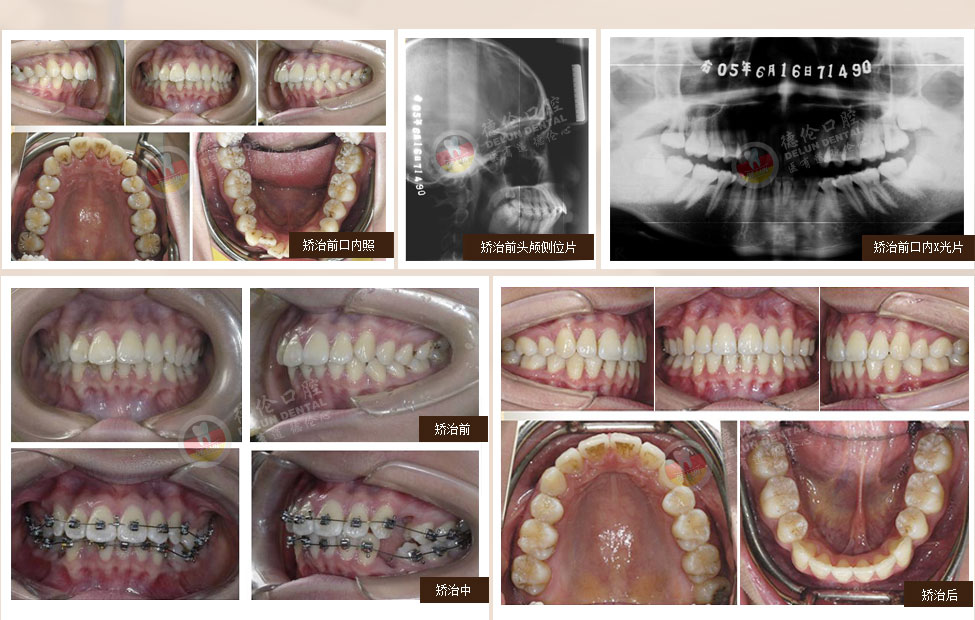

• 女:13歲

癥狀:上下前牙前突、唇傾,上下牙弓散在間隙

矯治方法:SPEED矯治器結(jié)合種植釘、整體內(nèi)收上下牙弓、改善雙牙弓前突以及凸面型側(cè)貌